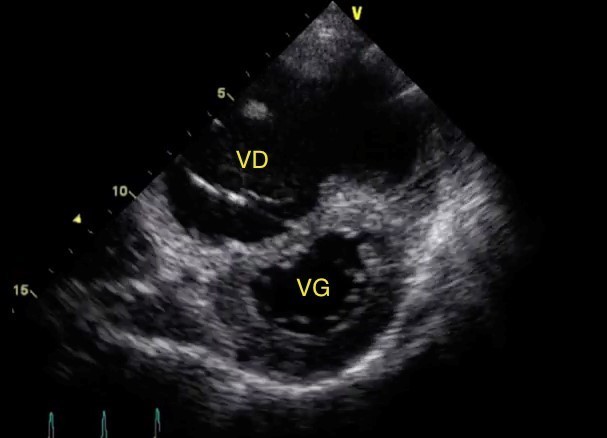

Voici les coupes de l’échographie cardiaque.

Coupe apicale 4 cavités :

* VD = ventricule droit, VG = ventricule gauche.

Les autres données de l’examen sont : une fonction ventriculaire gauche conservée, un débit cardiaque abaissé, une pression dans l’oreillette droite élevée avec une augmentation des pressions artérielles pulmonaires systoliques.

Aspect de cœur pulmonaire aigu (CPA)

Images évocatrices de CPA.

Caractéristiques d’un CPA :

– augmentation de la pression artérielle pulmonaire systolique (PAPS), évaluée sur l’insuffisance tricuspide ;

– dilatation du ventricule droit (VD) [rapport VD/VG > 0,9] que l’on voit ici ;

– inversion de la courbure septale (bombement septal vers la gauche en proto-diastole) que l’on voit ici ;

– puis dysfonction VD.